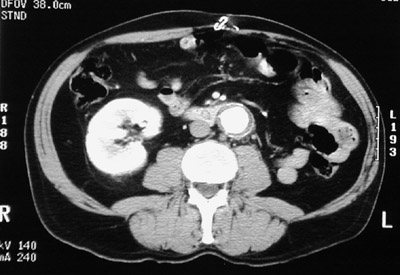

| In this abdominal CT scan with contrast the aorta is slightly dilated and the lumen is highlighted by contrast. Seen around the periphery is darker mural thrombus in a patient with severe atherosclerosis. The left kidney is absent from prior nephrectomy. |